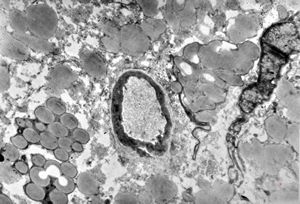

jejunum … lipid malabsorption